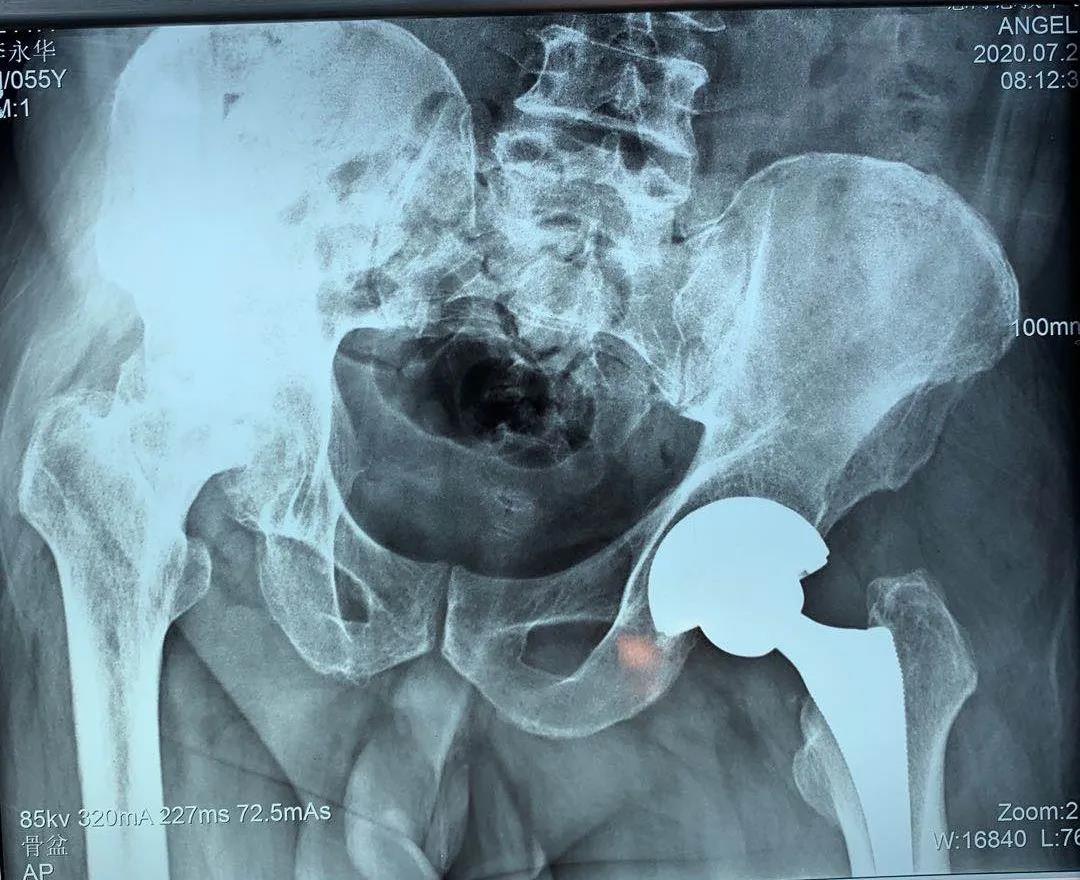

患者一年前雙側(cè)髖疼痛,到骨科就診,確診為股骨頭壞死,由于左髖關(guān)節(jié)痛疼較重給予行左髖關(guān)節(jié)置換,術(shù)后恢復(fù)良好。今年右髖關(guān)節(jié)痛疼加重再次住院,入院后完善相關(guān)檢查,根據(jù)患者病情,征得患者及家屬同意,順利施行了右髖關(guān)節(jié)置換術(shù),術(shù)前片子提示患者骨盆傾斜較重,術(shù)前評(píng)估設(shè)計(jì)術(shù)中假體植入角度,術(shù)后完美恢復(fù)雙下肢長(zhǎng)度與雙側(cè)髖關(guān)節(jié)旋轉(zhuǎn)中心,患者非常滿(mǎn)意,目前患者情況良好,已出院。

術(shù)前拍片